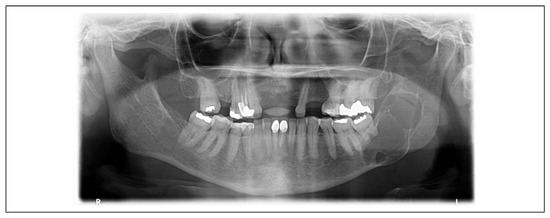

A Prospective Study on Autotransplantation of Mandibular Third Molars With Complete Root Formation

by Shishir Dhar, Gaurav Singh, Madan Mishra and Amit Gaur

Craniomaxillofac. Trauma Reconstr. 2022, 15(4), 340-349; https://doi.org/10.1177/19433875211055600 - 14 Mar 2022

Cited by 11 | Viewed by 435

Study Design: Autotransplantation, if possible, is a viable option for replacing a missing tooth when a donor tooth is available. The most typical tooth transplant is the transfer of a third molar to a first molar site. No immune reaction results from transplants [...] Read more.

Study Design: Autotransplantation, if possible, is a viable option for replacing a missing tooth when a donor tooth is available. The most typical tooth transplant is the transfer of a third molar to a first molar site. No immune reaction results from transplants of this nature. It restores the proprioceptive function and normal periodontal healing; thus, the patient can have a natural chewing feeling and natural biological response. Objective: This study aims to evaluate the prognosis of autotransplanted mandibular third molar and also to evaluate the cost effectiveness of the treatment performed when compared to the other treatment modalities for prosthetic rehabilitation. Methods: A prospective studywas done in theDepartment ofOral & Maxillofacial Surgery, Sardar Patel PostGraduate Institute of Dental &Medical Sciences, Lucknow,UP, India, with over 20 patients to evaluate the prognosis of autotransplanted mandibular third molars with complete root formation after atraumatic extraction of first or second mandibular molar, which were randomly selected irrespective of race, sex, caste, and socio-economic status. Regular clinical and radiographical examinations were performed over a period of 1 year and the patients were assessed for pain, swelling, infection, dry socket, periodontal pocket depth, ankylosis, root resorption, tooth mobility, and level of buccal bone in relation to cementoenamel junction (CEJ). Results: Eighteen out of 20 transplants were successful; only 2 mandibular transplants were extracted because of abnormal horizontal and axial mobility and the reason of failure was attributed to fact that the roots of transplant were short and conical and there was lack of alveolar bone height at the recipient site in one patient, while root resorption was the reason for failure of transplant in the other patient. Conclusions: This study assessed the efficacy of autotransplantation of molars and the viability of the procedure to replace unrestorable molar teeth; it also supports the hypothesis that transplantation of a mandibular third molar for replacement of a lost or seriously damaged molar tooth could be a reasonable alternative. Full article

Show Figures

Figure 1